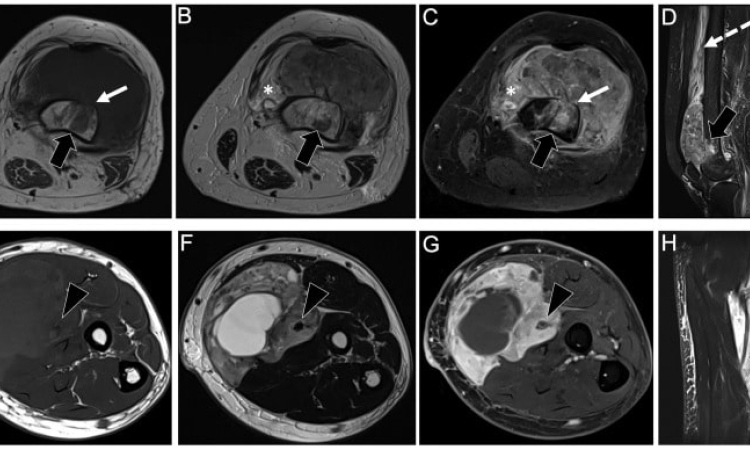

Также МРТ рекомендуется проводить при обследовании свежих или застарелых травм. Оно востребовано в направлении спортивной медицины для оценки степени тяжести повреждений, их последствий и эффективности реабилитационной терапии. Что показывает МРТПроцедура назначается при подозрении на воспалительные процессы, дегенеративные изменения или другие патологии в области мягких тканей лица, конечностей, шеи или туловища. Она показывает аномалии развития и патологические изменения исследуемых участков, в том числе лимфатических узлов, надкостницы, жировой клетчатки, связок. По результатам обследования принимается решение о необходимости хирургического вмешательства, проводится оценка послеоперационного состояния или результатов консервативного лечения. | |||||||||||